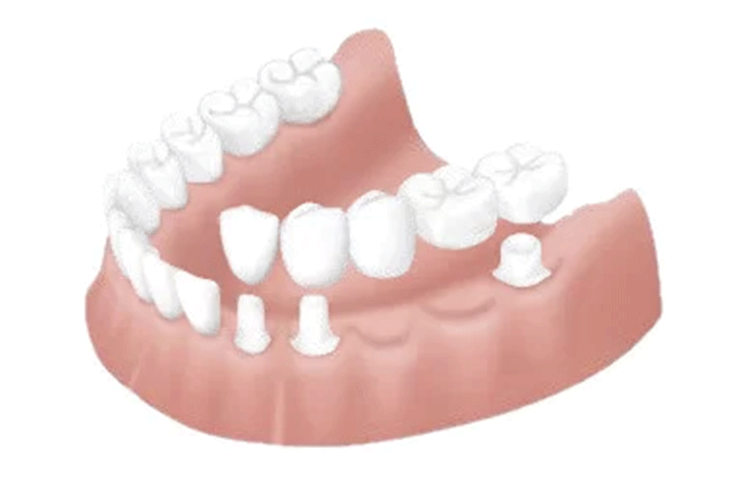

ブリッジ

失った歯の部分の左右の歯を削り、義歯(人工の歯)の橋をかける治療法